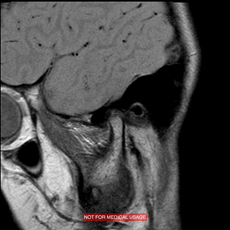

●MRI検査(顎関節症の診断 保険適応)

顎関節は噛み合わせの主要部分なので顎から音がする、ひっかかる、痛い、開けづらいなどの顎関節症状があった場合、顎関節の追加検査をすることがあります。